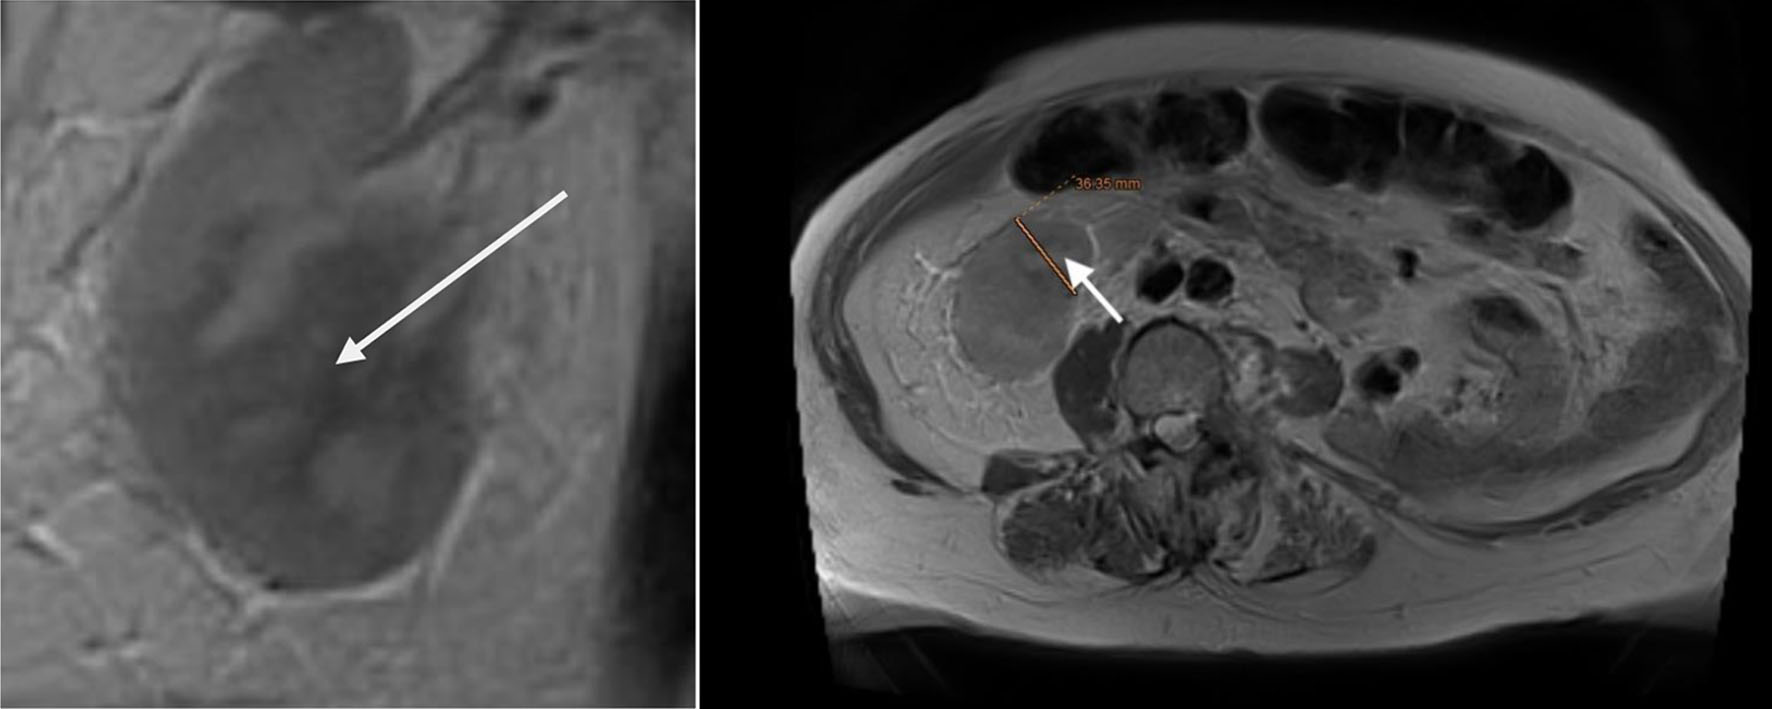

The patient, who had undergone a left nephroureterectomy 1 year earlier for urothelial carcinoma, presented again with suspected malignancy of the right upper urinary tract. Following urological consultation and instrumental evaluation (cystoscopy), urinary bladder tumors were detected, and the patient proceeded to further imaging assessment. Magnetic resonance imaging (MRI) of the upper abdomen revealed a tumor in the right kidney with invasion of the ureter and perirenal adipose tissue (Figs. 6 and 7). Lower abdominal MRI examination confirmed urinary bladder tumors with infiltration of the distal ureter and uterus (Figs. 811). Considering the patient’s clinical status, the potential aggressiveness of the malignancy, the absence of definitive histopathological confirmation of the new tumors (which could represent distinct lesions requiring separate pathological sampling), and the patient’s preference, no preoperative neoadjuvant therapy was administered. Surgery was therefore the only available therapeutic option, to which the patient provided full informed consent, despite her high-risk clinical profile and the complexity of the proposed high-risk surgical procedure. The postoperative histopathological report demonstrated high-grade renal urothelial carcinoma with contiguous extension to the ureter, urinary bladder, and bladder neck. Five of the 11 excised lymph nodes were metastatic, classifying the tumor as pT4N2Mx. Despite radiological evidence suggestive of uterine involvement, histopathological examination of the uterus and ovaries showed no malignancy; instead, polypoid endometrial hyperplasia and ovarian cysts were identified.

Figure 8. Lower abdominal magnetic resonance imaging (MRI) revealed a vegetative, infiltrative lesion invading the surrounding adipose tissue and occupying the urinary bladder cavity (arrow).

Figure 9. Lower abdominal magnetic resonance imaging (MRI) revealed a vegetative, infiltrative lesion invading the surrounding adipose tissue and occupying the urinary bladder cavity (arrows).

Figure 10. Lower abdominal magnetic resonance imaging (MRI) demonstrated an infiltrative tumor involving the urinary bladder and distal ureter (arrows 1 and 2), with extension into the uterus (arrow 3).

Figure 11. Lower abdominal magnetic resonance imaging (MRI) indicated possible infiltration of uterus (arrow).